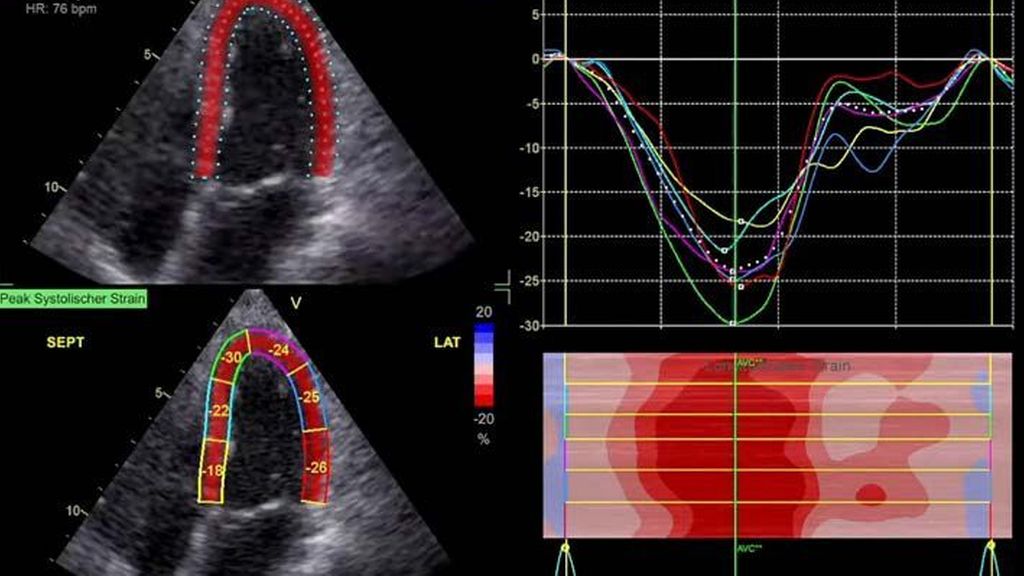

Die moderne Echokardiografie bietet die Möglichkeit einer hämodynamischen Evaluation in Ruhe wie auch bei „point-of-care“-Belastung. „Strain imaging“ und „myocardial work“ können neben bekannten Parametern, wie der Ejektionsfraktion (EF) und der Myokardmasse, ergänzend zur Diagnostik von Herzerkrankungen beitragen.

Im Echolabor des Pyhrn-Eisenwurzen Klinikums Steyr wird jede Form der Myokardwandverdickung mittels einer vollständigen Standardechokardiografie untersucht.2 Dabei wird auch ein Fokus auf die kontrastmittelunterstützte Sonografie gelegt, um die tatsächliche Dicke des Myokards zu vermessen.3 Die Verdickung sollte optimalerweise mittels 3D-LV-Massenmessung erfolgen. Die Messung im 2D-Bild ist dahingehend unterlegen. Ebenso wird jede Myokardwandverdickung mittels 2D-„strain imaging“ in der transthorakalen Echokardiografie (TTE) untersucht.4–6 Der „strain“ ist eine Messung der longitudinalen Funktion des Herzens (Video 1).

Der erste Fall beschäftigt sich mit einem Patienten mit einer hypertrophen Kardiomyopathie (HCMP). Er gibt eine deutliche Belastungsdyspnoe sowie einen ausgeprägten Leistungsknick an. Es wurde infolgedessen eine Untersuchung mittels standardisierter Echokardiografie inklusive „strain imaging“ durchgeführt. Der globale longitudinale „strain“ (GLS) mit –16% in Ruhe war gering reduziert. Es konnte kein relevanter LVOT-Gradient in Ruhe nachgewiesen werden. In der Belastungssituation (Handgrip, Valsalva, Kniebeugen und als Vorbereitung zur Untersuchung ein ausgiebiges Frühstück und Kaffee sowie ein am Vorabend konsumiertes Bier) konnte bei Kniebeugen mit einer Herzfrequenz von 126/min ein Spitzengradient bis 52mmHg dargestellt werden. Somit ergibt sich die Diagnose einer HOCMP mit einem belastungsinduzierten Gradienten. Bei bereits bestehender und ausgereizter Therapie unter Betablocker besteht die Indikation zur Therapie mittels des kardialen Myosininhibitors Mavacamten (Klasse-IIa-Empfehlung laut ESC).1 Darunter verbesserte sich die klinische Situation des Patienten deutlich, der Patient konnte uneingeschränkt Sport ausüben. Über die Zeit kam es zu einer geringen Reduktion der LV-Masse und einer geringen Zunahme des LV-„strain“. Die Belastungssituation zeigte durchwegs normale „strain“-Werte mit –20% (mit regionaler Reduktion bei Myokardwandverdickung im Sinne einer Hypertrophie). Die myokardiale Arbeit beim konkreten Patientenfall ist ebenso in Ruhe im grenzwertigen und unter Belastung im guten Normalbereich.6,8,9 Der Patient ist derzeit unter 5mg Mavacamten einmal täglich optimal eingestellt. Die EF in Ruhe ist konstant bei 50–55%. In Video 2 werden unterschiedliche Gradienten dargestellt, um eine HOCMP mit LVOTO von z.B. einer Mitralklappeninsuffizienz zu unterscheiden.Die Verdachtsdiagnose wurde mithilfe der Echokardiografie gestellt und durch das septal betonte „patchy“ LGE im MRT bestätigt.1,5

Andere Formen der Myokardwandverdickung, die mit „strain“ und MRT gut dargestellt werden können, sind einerseits die Differenzierung der Auswirkung der arteriellen Hypertonie (weiblich, 72a) bei Vorliegen einer Herzinsuffizienz mit normaler EF, einem GLS von –15,4%, einem LA-„strain“, in Reservoirphase 25% bei gering verlängerten T1-Zeiten im MRT. Andererseits kann Steroidabusus (männlich, 44a) zu einem reduzierten „strain“ mit gering verlängerten T1-Zeiten und einer Normalisierung der bildgebenden Befunde nach 2 Jahren nach Absetzen führen bzw. eine Mitochondriopathie (männlich, 32a) zu einer unklaren Myokardverdickung mit diffus reduziertem „strain“ und reduzierter LV-Funktion.4,11,12